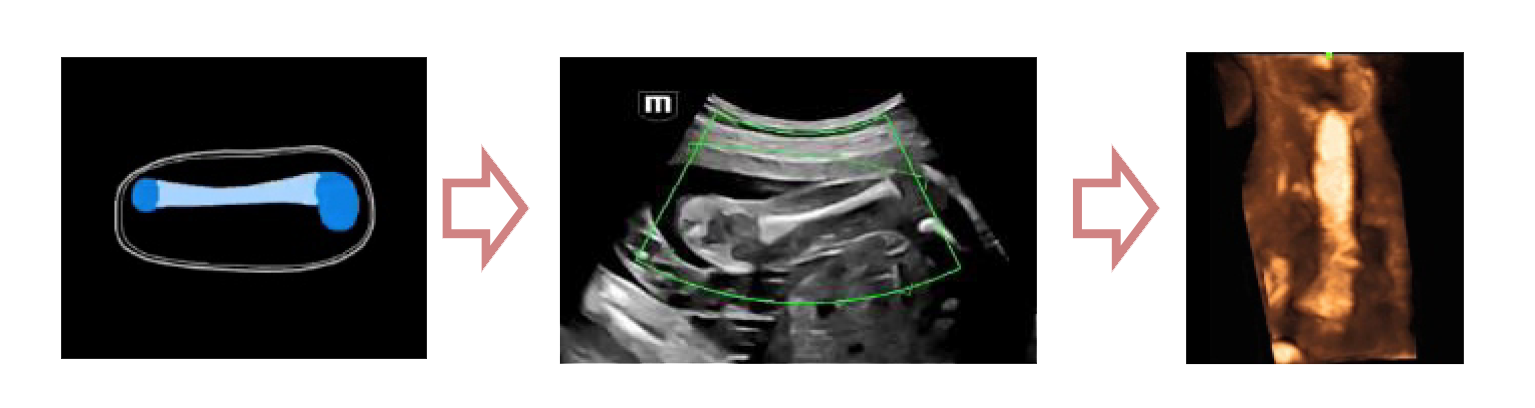

Легкое получение 3D изображения костей

- Автоматическое распознавание костей конечностей плода

- Автоматическая подстройка зоны интереса и положения до оптимального

- Автоматический рендеринг изображения

Место Smart Scene в технологии full-stack smartness